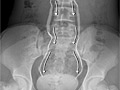

• An intravenous pyelogram (IVP). This is an X-ray test that shows pictures of the urinary tract and kidney stones.

• An abdominal X-ray (KUB). This creates a picture of the kidneys, the bladder, and the tubes that connect the kidneys to the bladder (ureters).